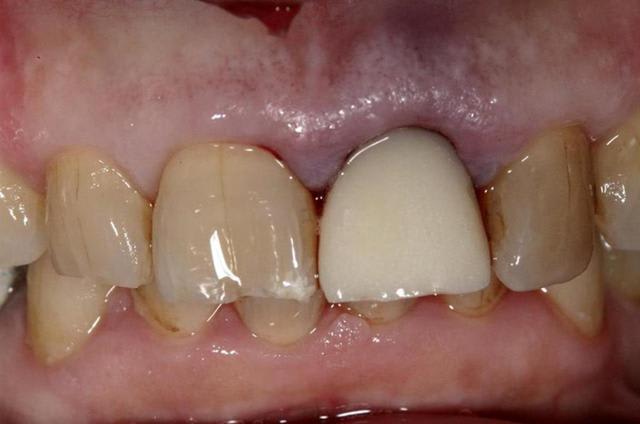

Allez, pour apporter mon caillou à la plage, un cas intéressant, d'implant en urgence.

consultation suite à une chute et fracture de 21 couronnée, un 29 Décembre, décision de poser l'implant le 31.12.

Extraction, mise en place d'un implant de 5*11.5 torque > 35N

Mise en place d'une dent provisoire transvisée.

Prothèse transvisée définitive à 3 mois.

Les 2 dernières photos à 1 an.

la photo ceram en place est à 6 mois. Noter l'amélioration des papilles entre 6 mois et 1 an...